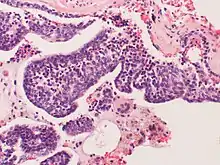

Pulmonary neuroendocrine cells (PNECs) are specialized airway epithelial cells that occur as solitary cells or as clusters called neuroepithelial bodies (NEBs) in the lung. Pulmonary neuroendocrine cells are also known as Kulchitsky cells or K cells.[2] They are located in the respiratory epithelium of the upper and lower respiratory tract. PNECs and NEBs exist from fetal and neonatal stages in the lung airways.

These cells are bottle- or flask-like in shape, and reach from the basement membrane to the lumen. They can be distinguished by their profile of bioactive amines and peptides, namely serotonin, calcitonin, calcitonin gene-related peptide (CGRP), chromogranin A, gastrin-releasing peptide (GRP), and cholecystokinin.

These cells can be the source of several types of lung cancer, most notably small cell carcinoma of the lung, and bronchial carcinoid tumor.[3][4]